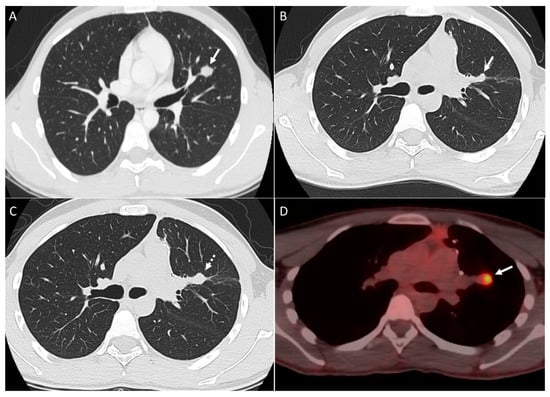

2.1. Parenchymal Metastasis

2.2. Vascular Metastasis